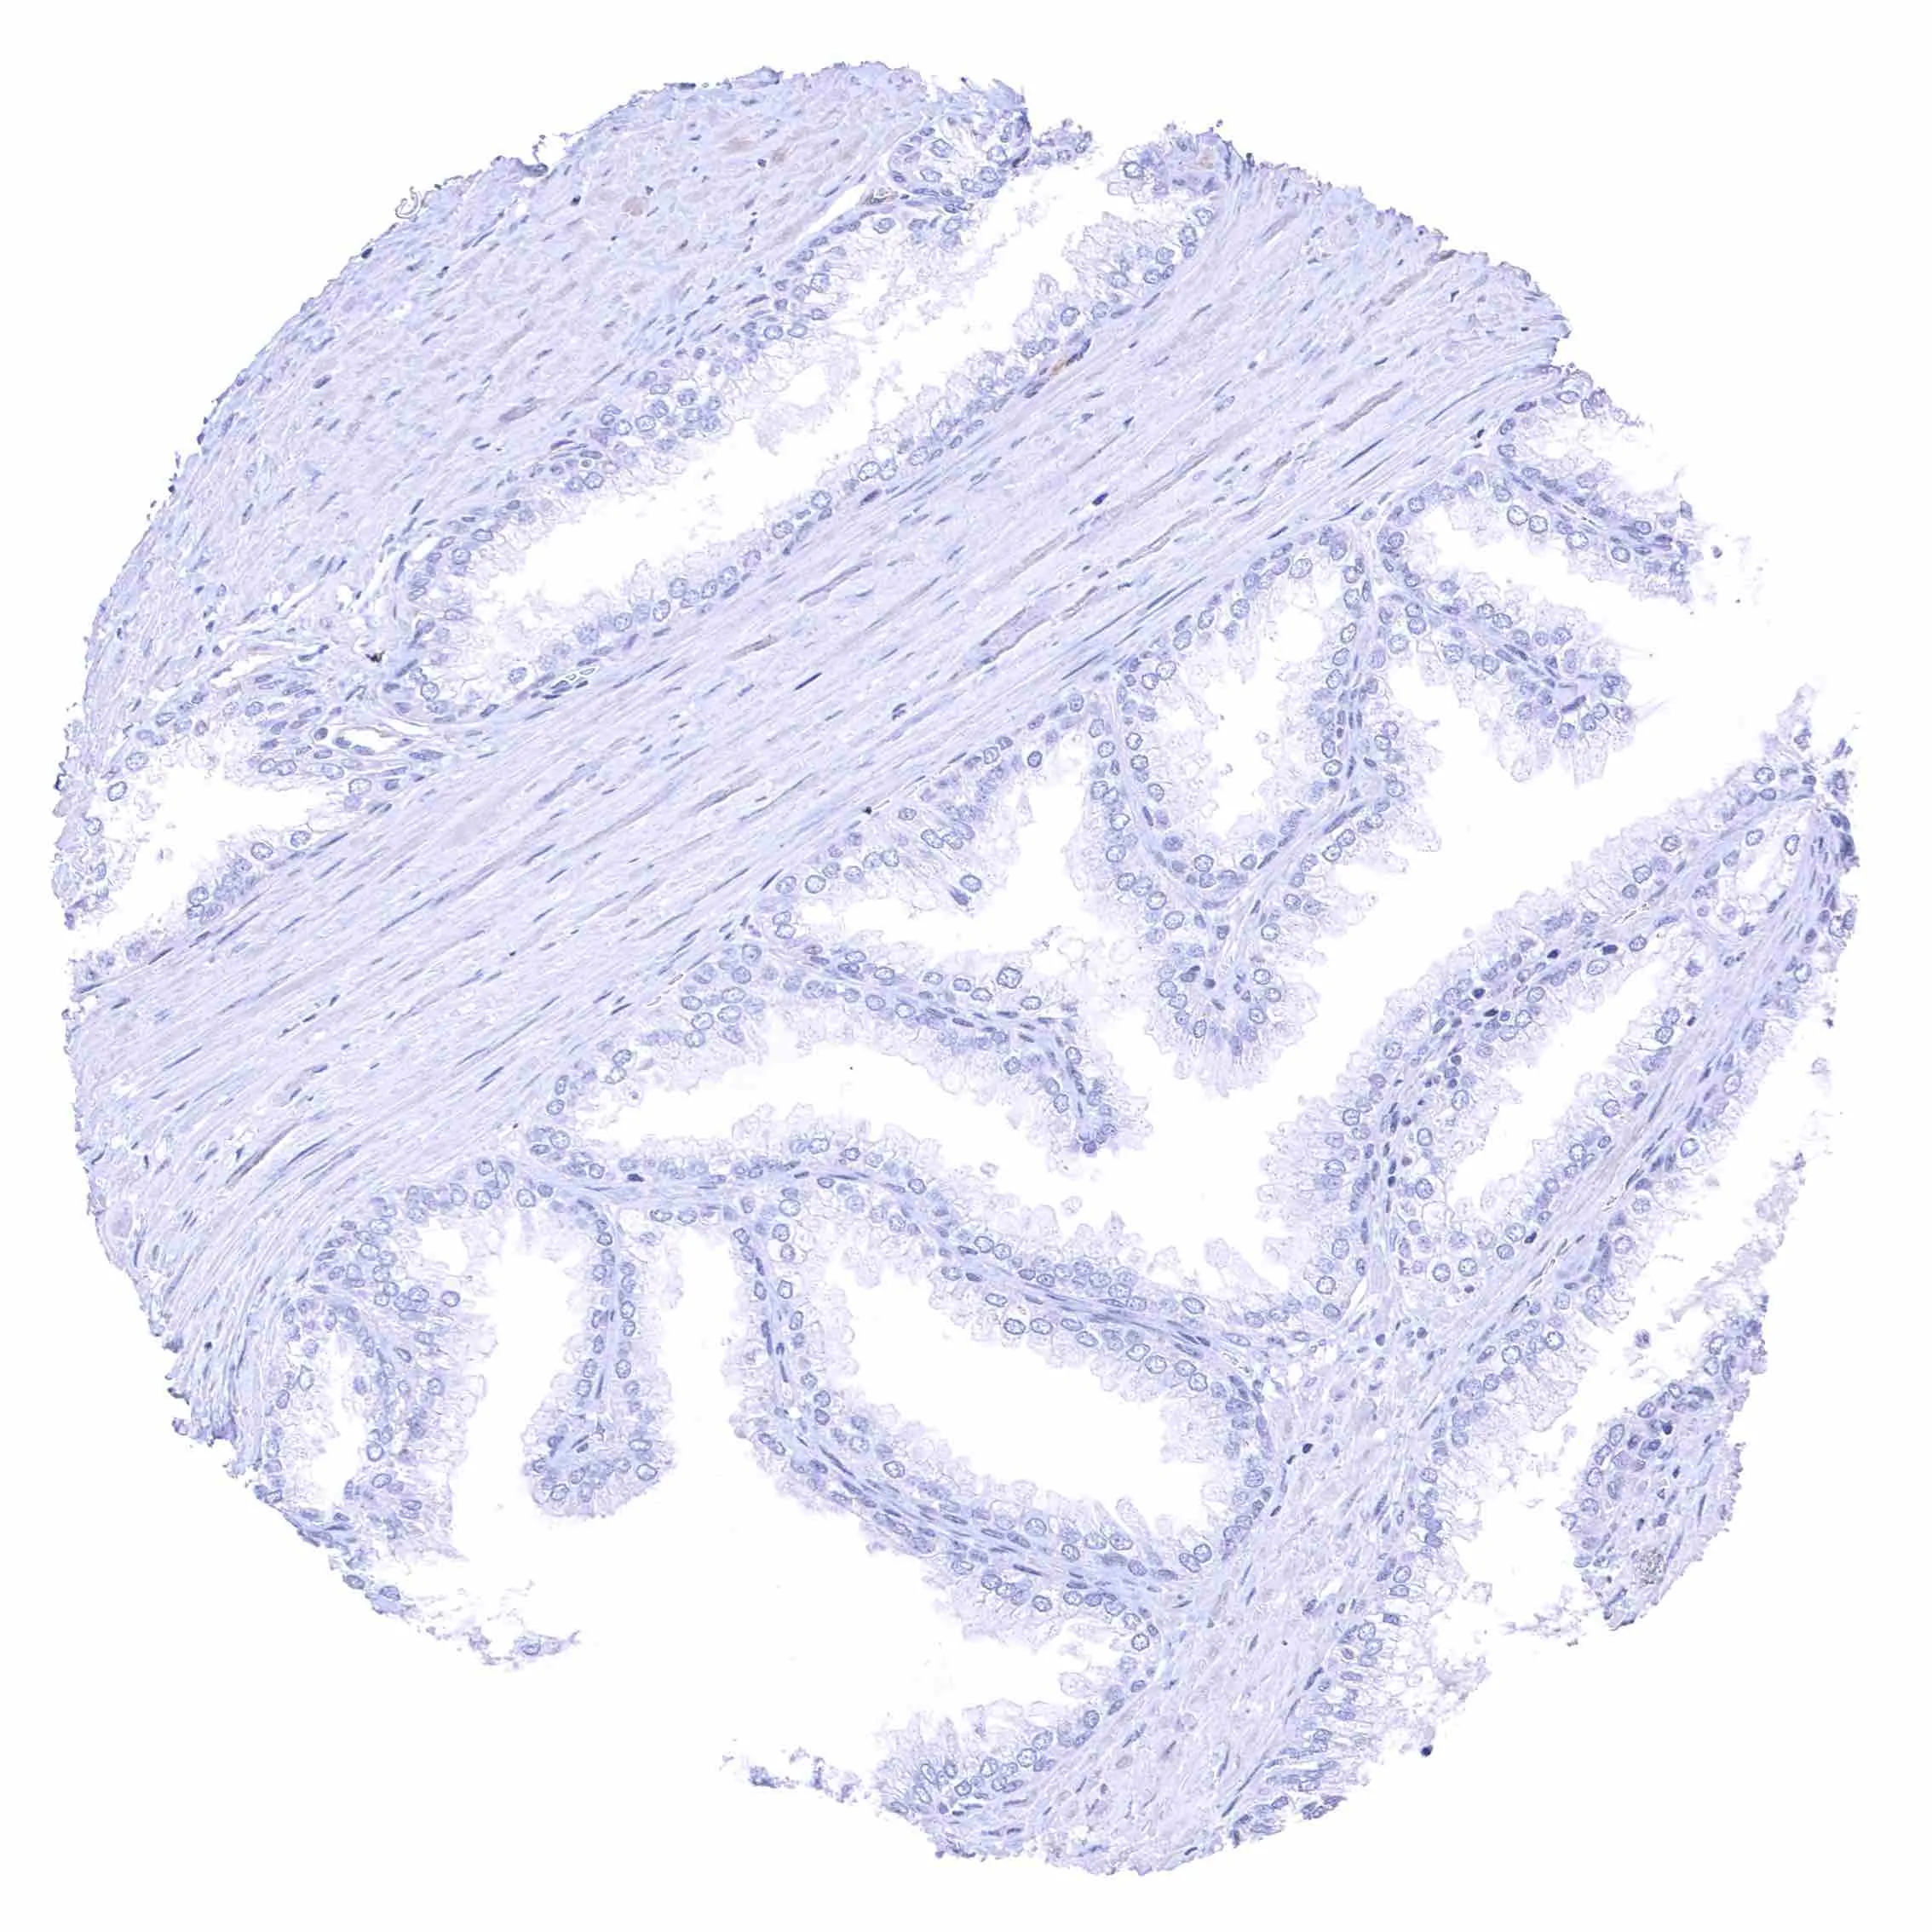

Fallopian tube, mucosa – Weak membranous NPR-C staining at the luminal cell border of endothelial cells of small blood vessels.

Uterus, endocervix